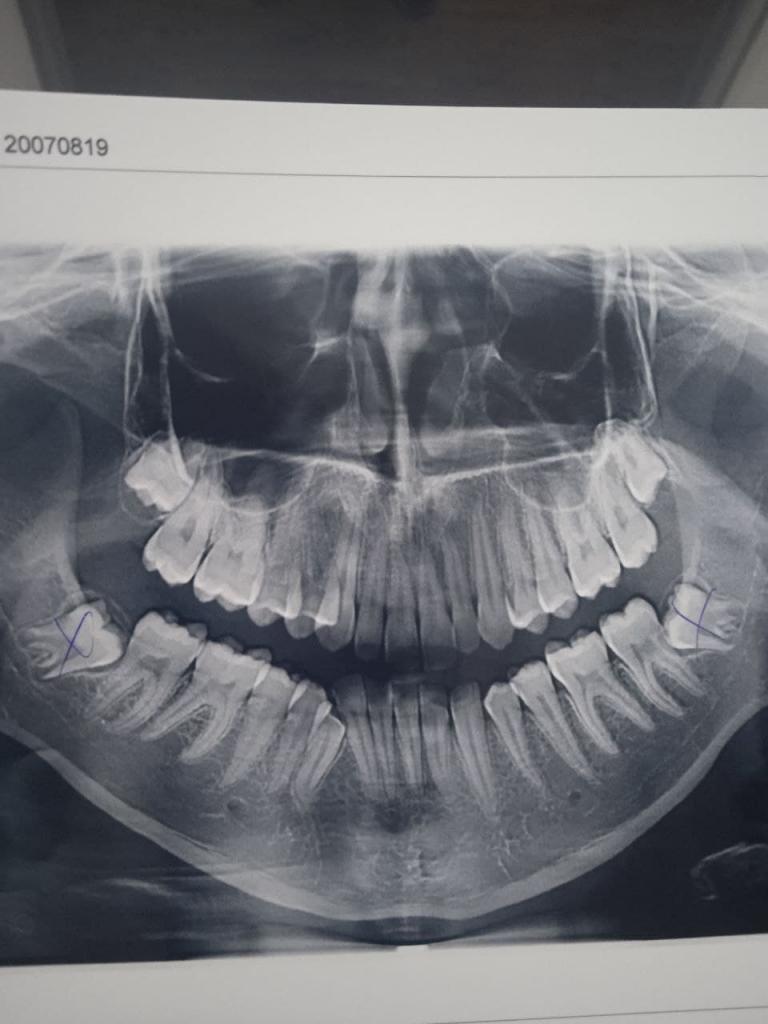

Нажмите на изображение для увеличения

Название: photo_2021-11-17_20-11-10.jpg

Просмотров: 48

Размер:	63.4 Кб

ID:	13529600

я так поняла, тут есть специалисты в чате.

Можете, пожалуйста. подсказать, нужно ли удалять эти нижние восьмерки? Или не стоит?

Специалист, конечно скажет надо, резать к чертовой матери, не доводя до перитонита.

Моей дочери, удалили такую восьмерку, когда началась боль, давление на 7-ку. Крестиком на КТ так же зачеркнули, после удаления. Многим писала по поводу хирурга отзыв, все прошло отлично, но не дешево. Потом удалила вторую нижнюю 8-ку, не лежачую, абсолютно здоровую. У нее пунктик, избавиться от всех 4-х.

А вот на вашем снимке, можно было бы и не удалять, ничего страшного не наблюдаю.